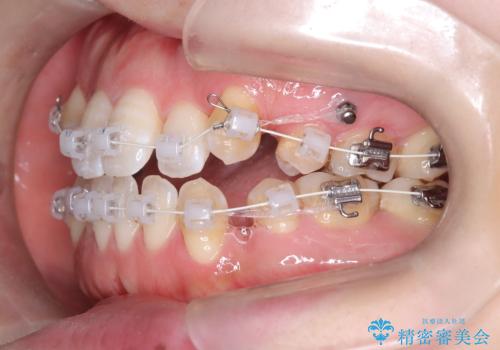

- 前歯のガタガタや八重歯の位置の乱れが気になっていた患者様に対して、ワイヤー矯正を行いました。矯正の過程で、スペースを確保するために上下左右の小臼歯を抜歯し、歯全体のバランスと機能性を考慮しながら理想的な歯列に仕上げました。

抜歯によって確保したスペースを活用し、効率的に歯列を整えました。前歯のガタガタと八重歯が解消され、自然で美しい仕上がりを実現しました。